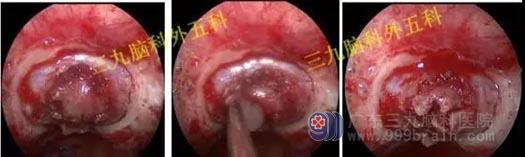

头部MR检查结果:鞍内及鞍上示一占位性病变,其内信号混杂,呈等或稍长T1稍长T2信号影,其内夹杂小片状短T1长T2信号影,增强后病灶呈明显不均匀强化;病灶范围约1.6cm×1.3cm×2.0cm;视交叉受压上抬,垂体柄受压右偏。

检查结果:鞍内及鞍上占位性病变,考虑为垂体大腺瘤合并卒中。

手术过程:患者今日在全麻下行内镜经鼻蝶鞍区垂体腺瘤切除术,术中肿瘤全切,垂体保护良好。

头部MR检查提示:鞍区病变已切除。